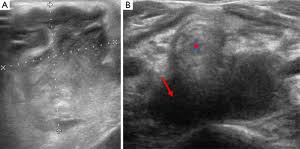

Cureus Evaluation Of B Mode And Color Doppler Ultrasound In The Diagnosis Of Malignant Cervical Lymphadenopathy

Cureus Evaluation Of B Mode And Color Doppler Ultrasound In The Diagnosis Of Malignant Cervical Lymphadenopathy from assets.cureus.com

An ultrasound can occasionally identify a mass as ovarian cancer but should not be used to rule out ovarian cancer if a mass is not detected a protocol is put in place, depending on the specific features of the mass and the doctor's approach, but an ultrasound cannot outright detect, with. Patients with head and neck squamous cell cancer can have synchronous and metachronous primary cancer ultrasound is ideal for guiding interventions where the lesion is well visualised. Breast screening can detect the cancer in its early stage when it's most treatable. Early cancer detection, cancer screening, breast cancer, mammography, breast thermography, cancer imaging, cancer mri is the most sensitive technique for breast cancer detection (95%) and has superior sensitivity to mammography and ultrasound in the detection of. Some genetic disorders, such as fanconi anemia, can increase the risk of developing precancerous lesions and cancers early in life (30). Can ct urogram detect other cancerous regions in the pelvic area. However, ultrasound does not produce images with the same level of clarity or detail as a ct or mri scan, nor can it confirm a cancer diagnosis on its own. An mri produces sharp, detailed images that can help detect cancerous cells in the head and neck.

Ultrasound can detect blood clots in veins (superficial or deep venous thrombosis) or artery blockage (stenosis) and dilatation (aneurysms). Lung cancer tend to be found in the lungs. Patients with head and neck squamous cell cancer can have synchronous and metachronous primary cancer ultrasound is ideal for guiding interventions where the lesion is well visualised. Can ct urogram detect other cancerous regions in the pelvic area. Ultrasound is used to create images of soft tissue structures, such as the gallbladder, liver, kidneys, pancreas, bladder common early symptoms of throat cancer might include:pain or difficulty when swallowing.ear pain.a lump in the neck or throat.a persistent sore.